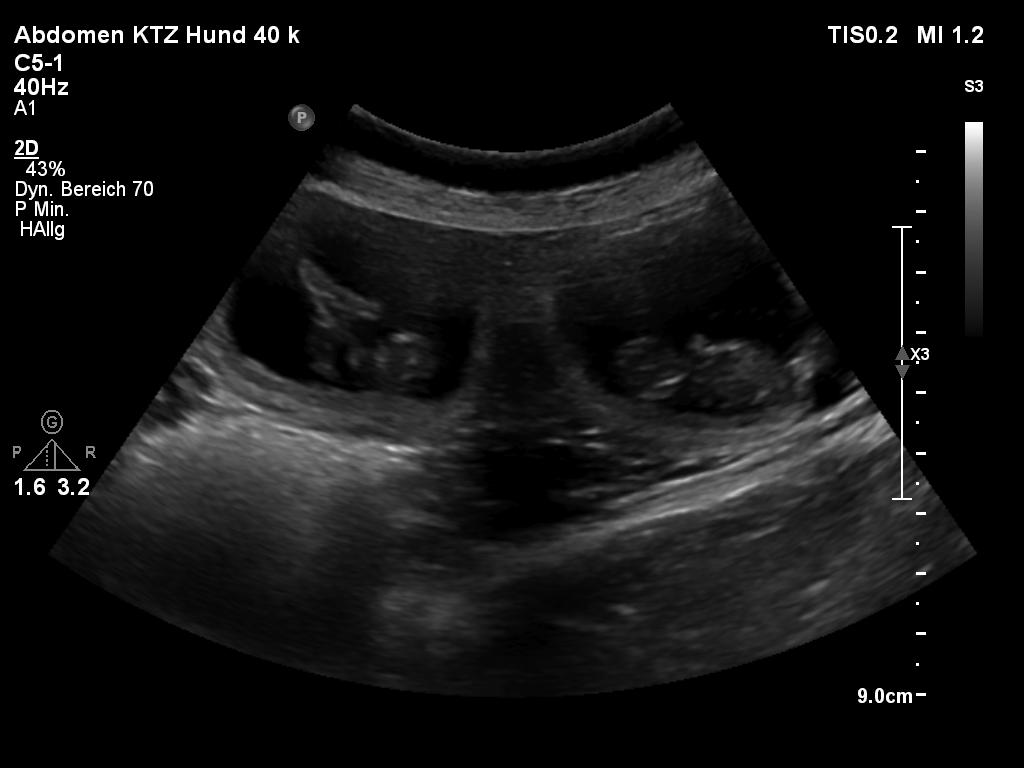

Heute waren wir beim Tierarzt zur Ultraschalluntersuchung.

Juhu - Jette ist tragend!!!! Die Welpen werden um den 03. Oktober 2025 erwartet.